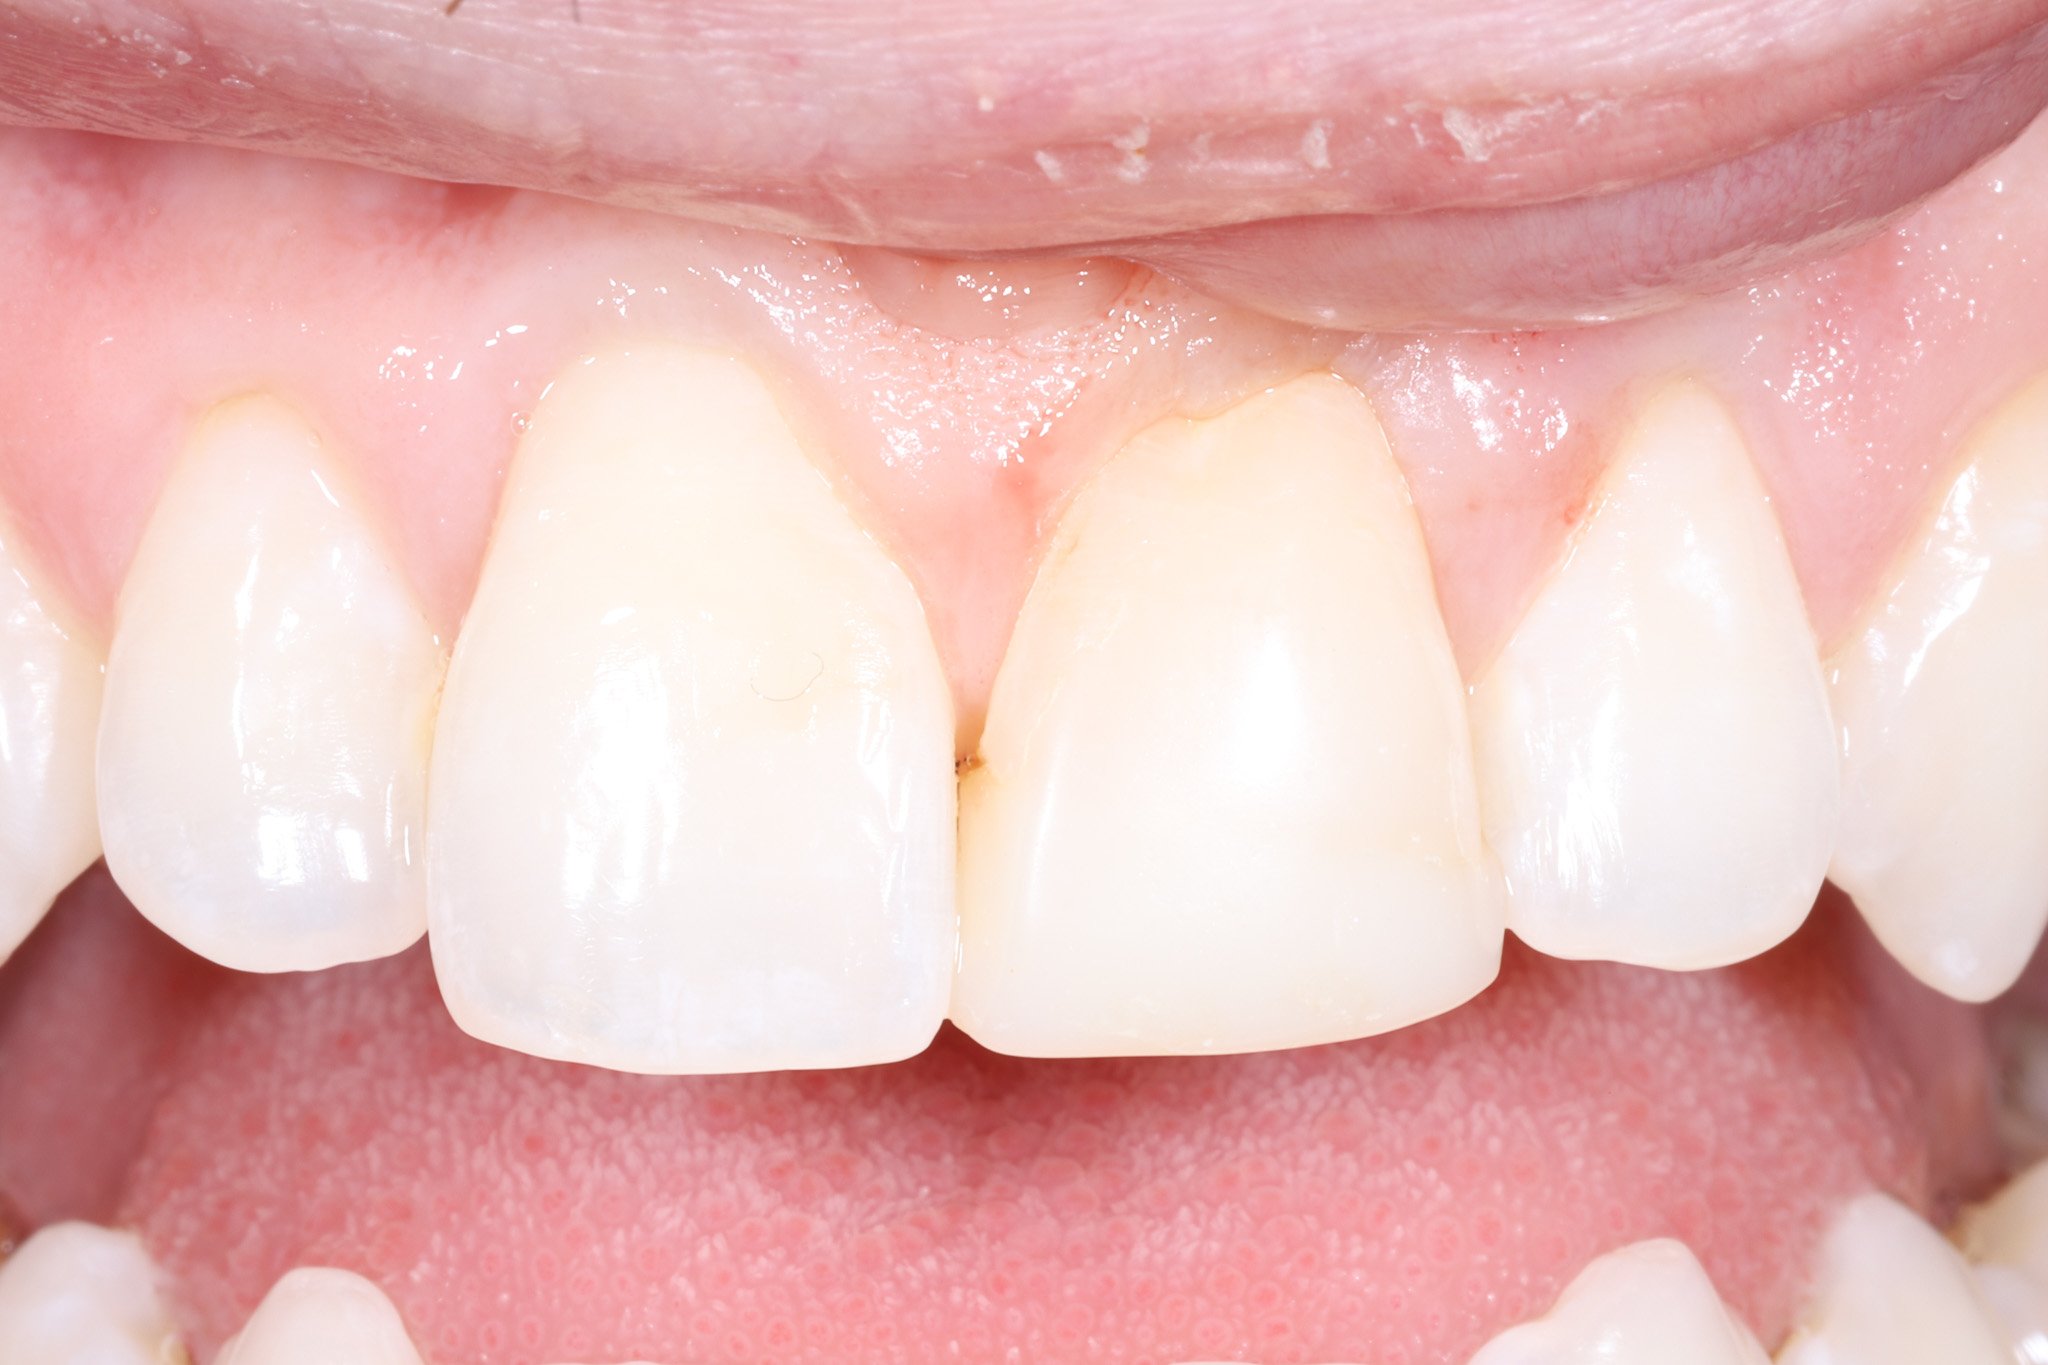

Close-up of a person's upper front teeth, showing slight misalignment and a small gap between the two front teeth.

Before: White filling that doesn’t match in shape and color

Close-up of upper front teeth and gums with natural appearance.

After: Bonded porcelain restoration that blends seamlessly and protects underlying tooth structure